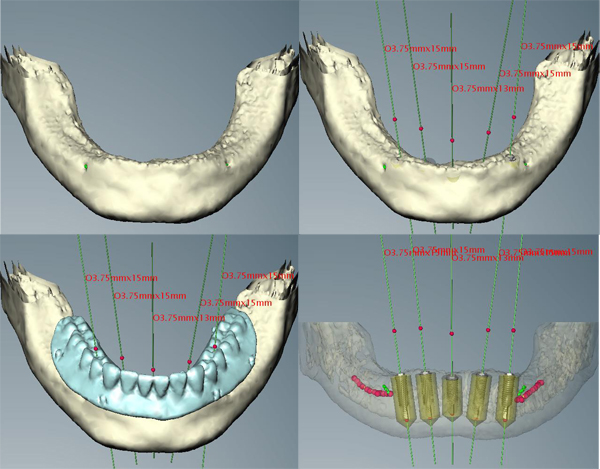

このケースは事前に撮影したCT画像をコンピュータ解析し,歯ぐきを切らずにインプラントを埋め込む方法です。

このケースは事前に撮影したCT画像をコンピュータ解析し,歯ぐきを切らずにインプラントを埋め込む方法です(当院の患者様ですが,当院で初めてのケースでしたので奈良県五條市にある中谷歯科医院の堀内克啓先生にご協力いただきました)。

CT解析画像

歯ぐきを切らないでインプラントを入れ,その日のうちに「仮の歯」を入れました。写真は手術翌日ですが,歯ぐきの腫れはほとんどありません。食事も柔らかい物であれば手術直後から普通に出来ました。